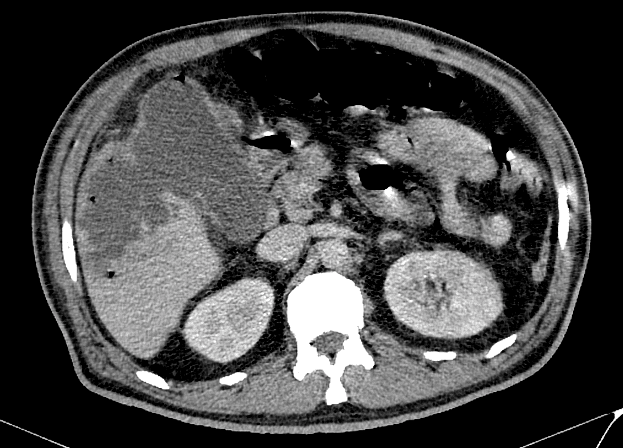

Viêm túi mật

» Thông tin: Nam giới – 60 tuổi.

» Lâm sàng: Đau bụng cấp.

# Viêm túi mật cấp biến chứng vỡ => Apxe gan.